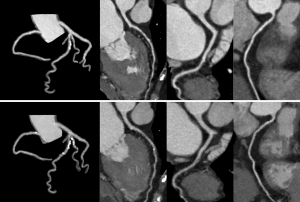

The Kaplan-Meier curves showed that the cumulative event-free survival rates of the DM and non-DM groups were 60.4% and 78.1%, respectively (log-rank test, P<0.001) (Figure 3A). The cumulative event-free survival rates based on the presence or absence of DM and atherosclerosis progression were also calculated using Kaplan-Meier survival estimates (Figure 3B). The DM group with atherosclerosis progression had the lowest event-free survival rate (49.1%) among the four groups (log-rank test, P≤0.006), followed by the non-DM group with atherosclerosis progression (73.6%). The cumulative event-free survival rate was lower in the non-DM group with atherosclerosis progression than in the non-DM group without atherosclerosis progression (73.6% vs. 87.9%; log-rank test, P=0.001). The event-free survival rate of the DM group without atherosclerosis progression was similar to that of the non-DM group without atherosclerosis progression (82.7% vs. 87.9%; log-rank test, P=0.345). However, no differences were observed between the DM group without atherosclerosis progression and non-DM group with atherosclerosis progression (82.7% vs. 73.6%; log-rank test, P=0.328). A representative case of DM with atherosclerosis progression is presented in Figure 4.